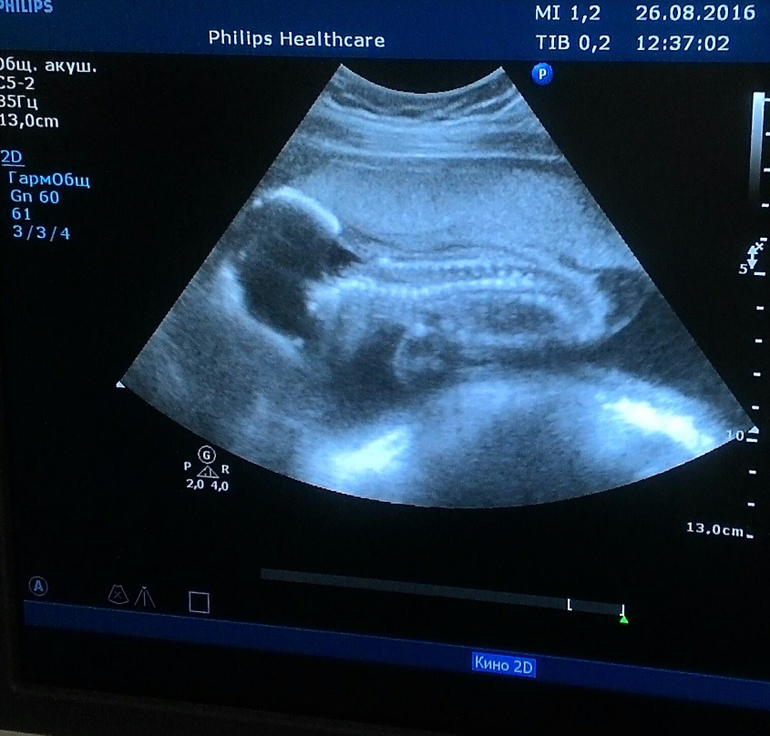

26 числа мы были на узи в ЖК, я хоть и ничего не видела, и фотку сделала со стоп кадра на мониторе! но даФольна как слониха!)))

смотрю на фотку и слюна течет! мой малыш, такой уже сладенький, не могу!!!!! попа такая))))

тут он лижит мордашкой вниз, слева голова, справа попа) спинка моя сладенькая))) ее уже даже погладить могу, когда выпирает кабачком то справа, то слева))) под животиком ножка согнута, и левую ручку палец сосет)

Все хорошо, все работает,все в норме, только селезенку не дал рассмотреть)

а так: мы уже 500 грам!!!!!

рост 29 см!!!

мы даже на день больше срока)

стопа у нас 3,7 см!)))) и пяточку причем замеряли почти под ребрами) Хотя все основные шевеления ощущаю ниже пупка, а выше ооочень редко и вот как первые шевеления, как проплывает что-то))))

вот такой у нас мышонок уже, он же кабачок)

уже распознаю когда и чем толкает, 2 раза слышала как икает))) 4 день будит меня по утрам, но не раньше 8 утра))) начинает толкать))) вчера на ночь наелась арбуза-пинал всю ночь в мочевой)))) впервые в среду попал, так неожиданно было)